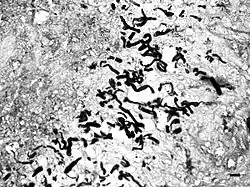

It is suspected that pythiosis is caused by invasion of the organism into wounds, either in the skin or in the gastrointestinal tract.[2] The disease grows slowly in the stomach and small intestine, eventually forming large lumps of granulation tissue. It can also invade surrounding lymph nodes. Symptoms include vomiting, diarrhea, weight loss, a mass in the abdomen, and depression. Pythiosis of the skin in dogs is very rare and appears as ulcerated lumps. Primary infection can also occur in the bones and lungs.